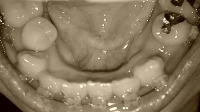

以下、画像です。

060905g.jpg 5月19日

beforeU.jpg 5月?日(抜歯前)